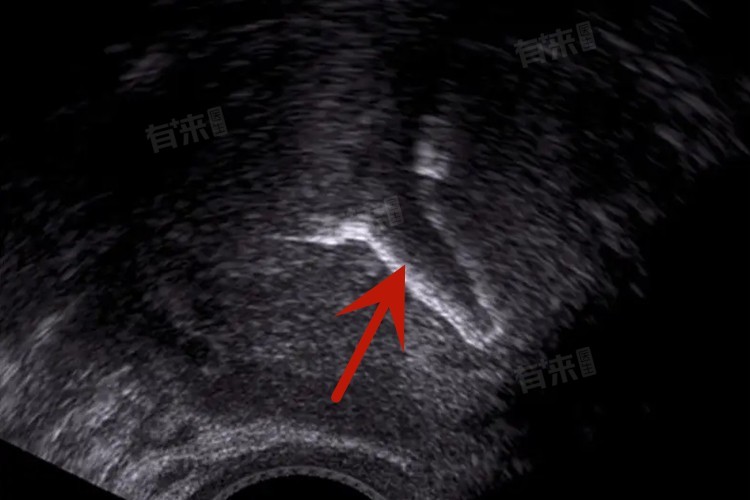

4、环的位置和状态:定期检查中发现环位下移、变形或损坏,应及时取出,通常在发现异常后的1个月内。环位置正常且功能良好,可按常规5-7年取出。